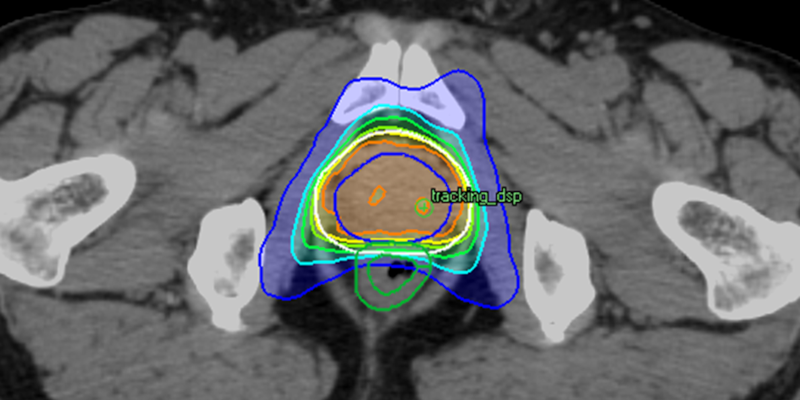

当院では、前立腺がんに対してIMRT、VMAT、さらにVMATを発展させたDWAを用いて高精度で身体への負担が少ない放射線治療を行っています。 現在はDWAを主に用い、短時間での照射を維持しながら、がんに放射線を集中させ、周囲の臓器への影響を抑えた治療を提供しています。

強度変調放射線治療(IMRT)は、専用のコンピュータを用いて放射線の強さや当て方を細かく調整し、がんの形に合わせて照射を行う治療法です。複数方向から放射線を当てることで、前立腺に高い線量を集中させながら、膀胱や直腸など周囲の臓器への影響を抑えることができます。

DWA(Dynamic Wave Arc)― VMATをさらに発展させた治療

当院では2023年より、VMATをさらに発展させたDWA(Dynamic Wave Arc)による治療を導入しています。DWAは、Vero4DRTという装置の特長を活かした照射方法で、VMATと同様に短時間での照射が可能です。治療時間自体はVMATとほぼ変わりませんが、通常の回転照射に加えて装置のリング部分も動かすことができるため、より多方向から立体的に放射線を当てることが可能になります。これにより、がんの形によりよく合わせた照射ができ、周囲の正常な臓器への影響をさらに抑えた、より精度の高い治療を行うことができます。

現在、当院の前立腺がんに対する放射線治療では、DWAを主に用いています。

前立腺がんに対するDWA照射

当院では、治療装置に内蔵された CBCT(コーンビームCT)装置を用いて、治療直前に前立腺周囲の画像を撮影し、臓器の位置を確認しています。 このため、体内に金マーカーを埋め込むことなく、前立腺の位置を確認・補正しながら、安全で精度の高い放射線治療を行うことが可能です。加えて、2023年に治療計画を作成する専用のコンピュータを更新し、DWA(Dynamic Wave Arc)による治療が可能となりました。これにより、以前よりもさらに前立腺に放射線を集中させながら、直腸への線量を効果的に抑える線量分布を作成できるようになりました。そのため、体内にハイドロゲルスペーサーを注入する処置を行わなくても、安全性に配慮した放射線治療が可能となっています。これにより、金マーカーやハイドロゲルスペーサーを体内に入れるという処置の侵襲を避けながら、安全性と治療精度の両立を図っています。